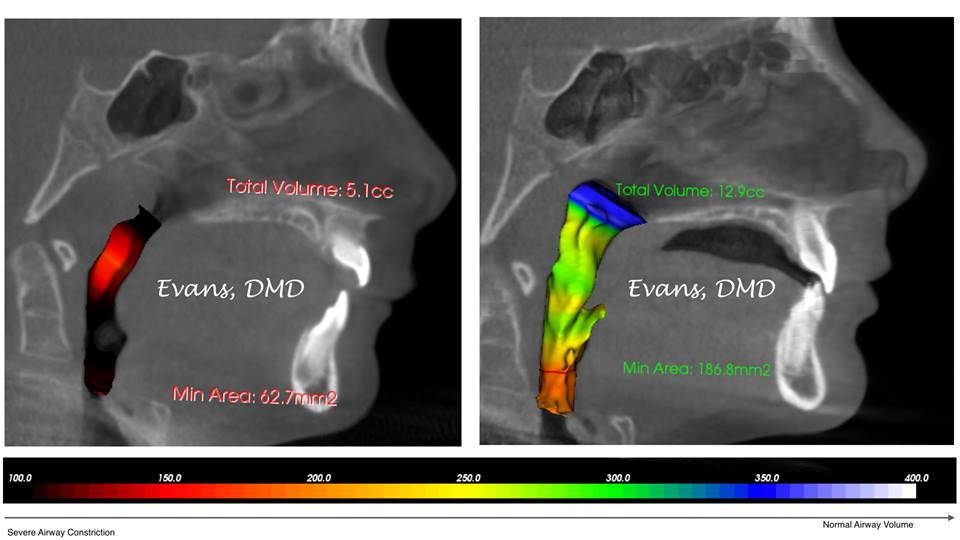

Thankyou. I know I'm recessed and the orthodontist agrees but he says that recession isn't severe.theyre gonna give me the results with tracing on January 5th.Yes you're recessed, you also seem to have a bit of a shitty/reduced posterior airway aswell

View attachment 4482242